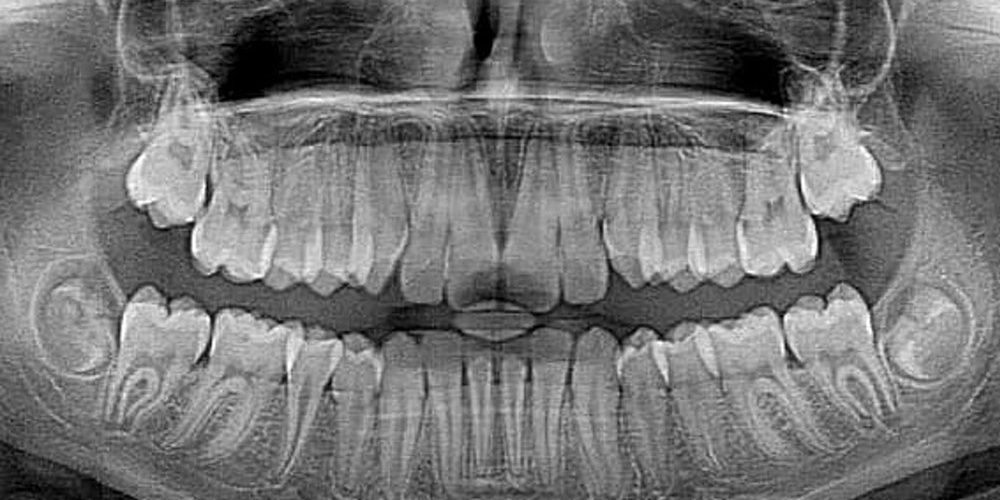

Кальциноз сонной артерии – признак прогрессирующего атеросклероза, который может быть связан с хронической коронарной недостаточность (КН) и может привести к смерти. Такой кальциноз можно увидеть при обычной панорамной рентгенографии полости рта.

«Инфекции полости рта довольно распространены, но они часто являются латентными и обнаруживаются только при рентгенографии. Рентгенограммы всей челюсти, проведенные в сочетании со стоматологической помощью, могут выявить риск сердечно-сосудистых заболеваний. Если на рентгенограмме виден кальциноз сонной артерии, пациента необходимо направить на дальнейшие обследования», — рассказывает доцент Пиркко Пуссинен из Хельсинкского университета.